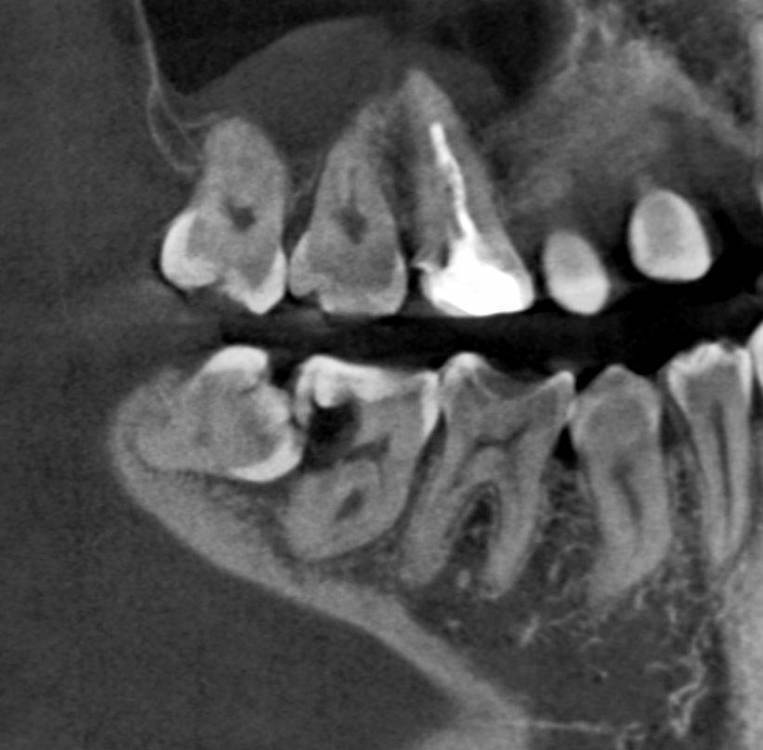

Петрович Опубликовано 4 февраля, 2024 Поделиться Опубликовано 4 февраля, 2024 Чтобы они не вредили нижним 7. Планируется: брекеты и имплантация 3.6 через год - в 14 лет. Ссылка на комментарий

Bier Опубликовано 5 февраля, 2024 Поделиться Опубликовано 5 февраля, 2024 планируется ортодонтия, 8ки мешают по плану лечения. После формирования корней - удаление будет сложнее и риск осложнений вырастет. 1 Ссылка на комментарий

Bier Опубликовано 5 февраля, 2024 Поделиться Опубликовано 5 февраля, 2024 ну еще действует аргумент, что они сейчас мешают дистализации зубов. Еще аргумент: могут быть причинами рецидива ортодонтического лечения. Удаляю такие зачатки часто. 12-16 лет пациентам. Ссылка на комментарий

Женька Опубликовано 8 февраля, 2024 Поделиться Опубликовано 8 февраля, 2024 @karasov снимок Мартовского как бы намекает как бывает. Когда зуб был ведь зачатком. А что до Радлинского и Щербакова так пусть спорят. В МСК и других сильно крупных городах может и не скалываются пломбы (не верю). У меня же статистика другая) Ссылка на комментарий